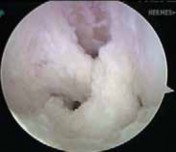

29. This process is then repeated for the PM graft (

TECH FIG 8

).

1. It is helpful to keep tension on the AL graft suture ends when passing the PM graft to ensure that the AL graft does not get pulled into the joint.

--- TECH FIG 8 • The double-bundle reconstruction with the grafts in place. ### TECHNIQUES